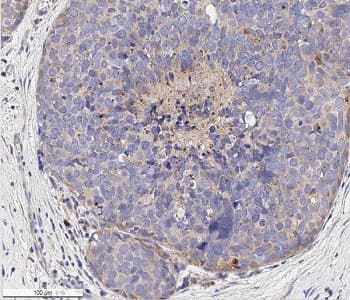

Anti-VEGF Receptor 1 + VEGF Receptor 2 antibody(ab36844)

Rabbit Polyclonal VEGF Receptor 1 antibody. Suitable for WB, IHC-P, ICC/IF and reacts with Mouse, Human samples. Cited in 9 publications. Immunogen corresponding to Synthetic Peptide within Mouse Flt1 aa 800-900.

Applications ICC/IF, IHC-P, WB

Species Reactivity Human, Mouse